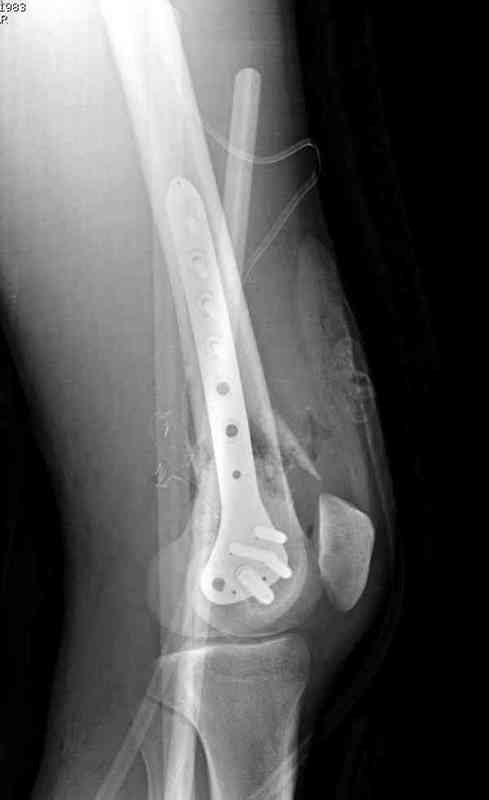

Латерально пластину защитили ушиванием

илио-тибиального тракта, а медиальная сторона была ушита мышцей, и все раны закрыли ваккумированием (VAC)

На третий день после Irrigation & Debridment закрыли все раны за исключением компартментальной раны из-за отека, медиально в дефект кости установили Putty Grafton Bone Substitute. На компартментальную рану вакуум и мероприятия по сближению краев раны резиновой стяжкой.

На 9й день с момента травмы ушили рану без натяжения. Больной получает реабилитацию, движения коленного сустава с помощи CPM-continuous passive motion machine. Сегодня выписан.